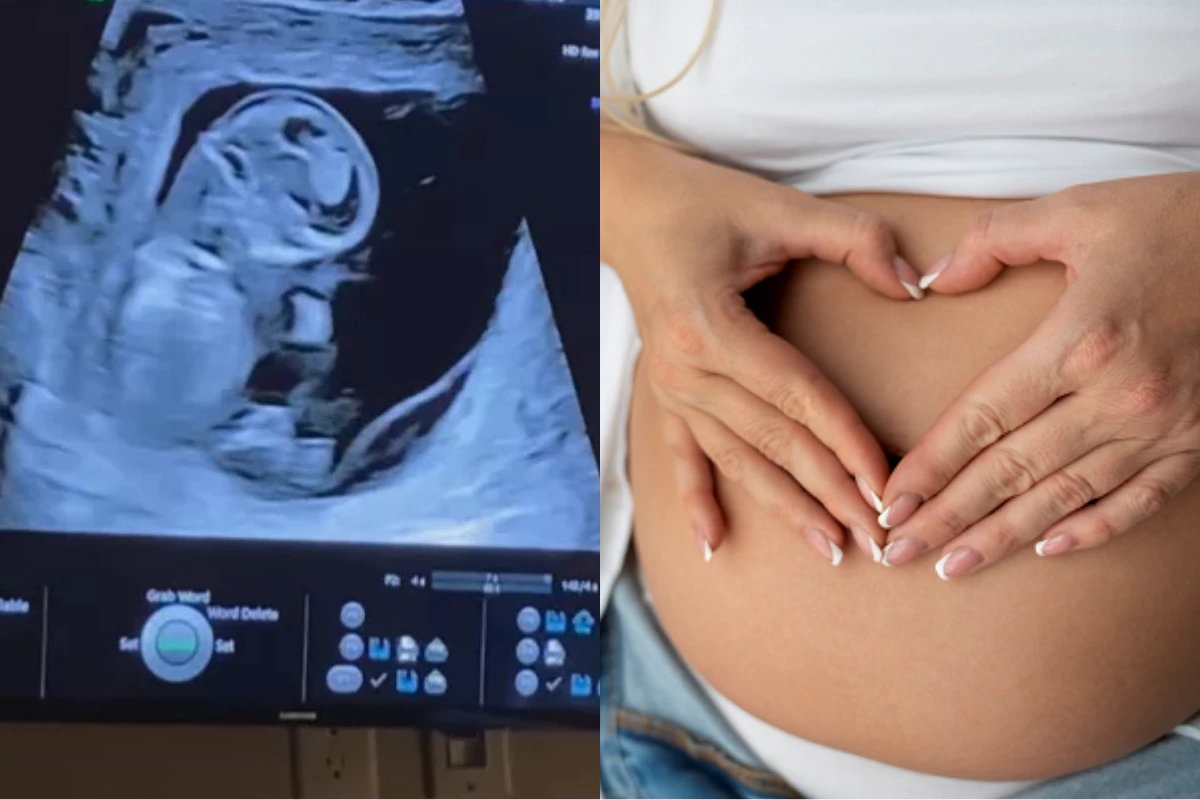

Quando Elizabeth e Joshua Evans receberam o diagnóstico de Trissomia 18 para seu filho, Joshy, ainda na 14ª semana de gestação, a notícia indicava uma condição genética rara e grave – geralmente incompatível com a vida. Os médicos foram claros sobre o prognóstico: o bebê não sobreviveria.

Essa escolha de celebrar a vida de Joshy, apesar do prognóstico desafiador, foi documentada pelos pais. Elizabeth compartilhou um vídeo emocionante no Instagram, que comoveu milhões de pessoas e alcançou mais de 26,5 milhões de visualizações. A mãe escreveu na postagem: “Criamos muitas memórias para lembrar do nosso bebê”. Em meio ao luto antecipado, o casal encontrou uma forma de transformar a dor em lembranças concretas, repletas de afeto e conexão com o filho.

Elizabeth e Joshua decidiram proporcionar a Joshy uma vida plena, mesmo sabendo que seria breve. Durante a gravidez, eles realizaram diversas atividades simbólicas: cantaram para o bebê, leram histórias, cozinharam juntos, celebraram datas importantes como o Dia de Ação de Graças e decoraram a casa para o Natal. Na noite anterior ao parto, realizado com 36 semanas, organizaram uma festa de aniversário para o filho. Cada movimento do bebê na barriga era motivo de celebração, e cada ritual representava uma forma de expressar amor e valorizar a existência de Joshy.